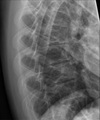

Give 3 differentials in order of likelihood.

(Erlenmeyer flask deformity) 1. Thalassemia 2. Sickle cell anemia 3. Osteopetrosis

Give 2 differentials in order of likelihood.

1. Thalassemia 2. Sickle cell anemia